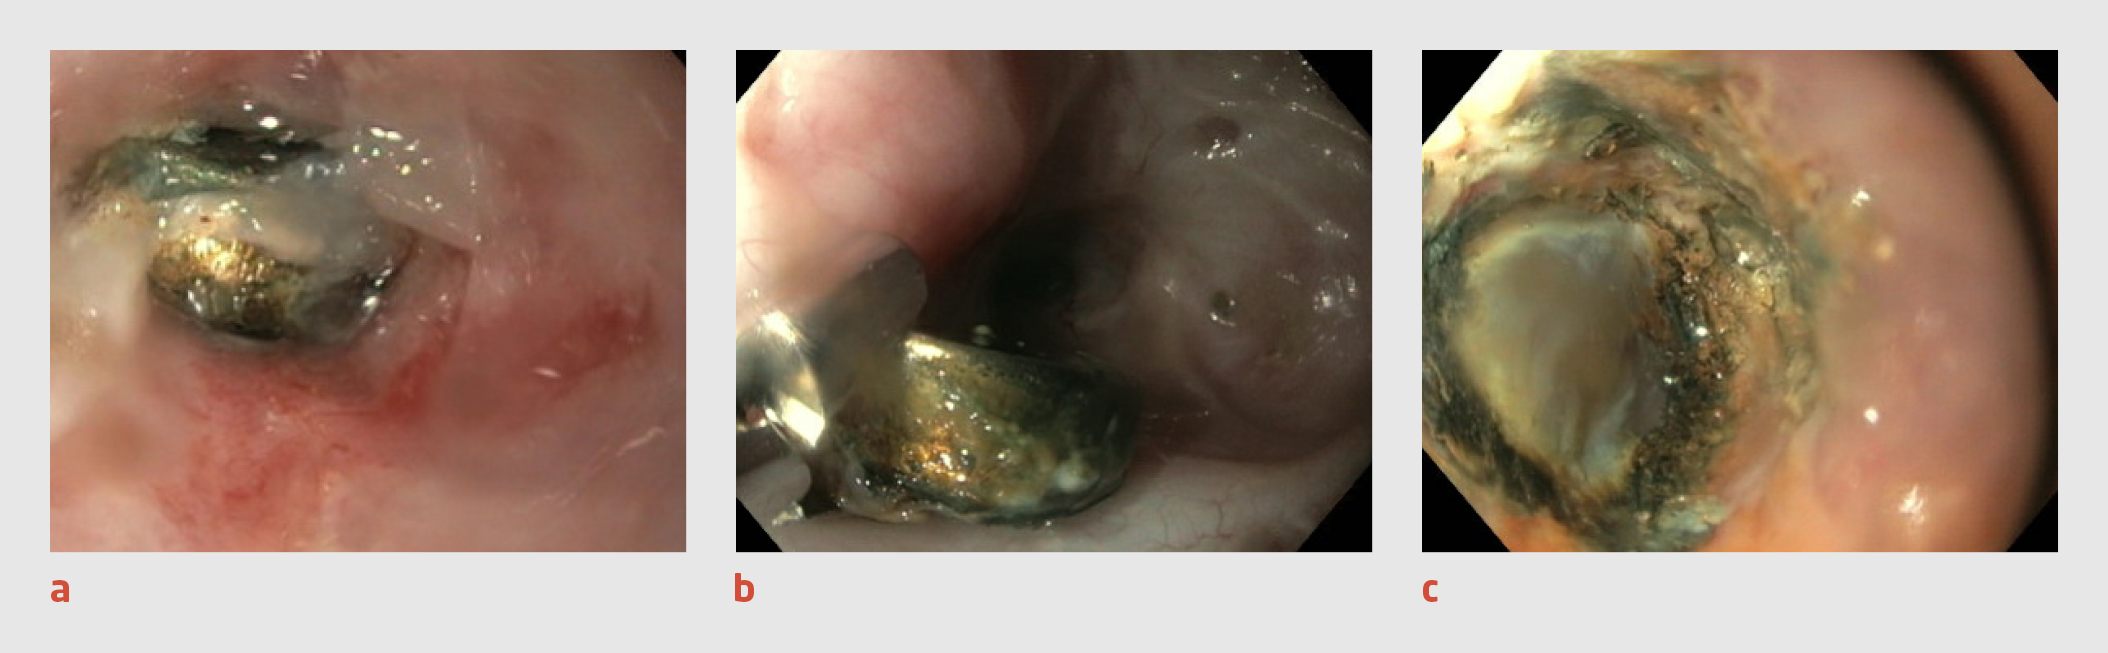

Figuur 3

Ingeslikte knoopcelbatterij

Figuur 3 | Ingeslikte knoopcelbatterij

Beelden bij gastroscopie van patiënt C. (a) In de slokdarm wordt op 25 cm van de tandenrij een knoopcelbatterij aangetroffen. (b) Na spoeling van de oesofagus komt de batterij los te liggen en kan deze verwijderd worden. (c) Na verwijdering van de batterij zijn bij inspectie van de slokdarmwand forse druknecrose en débris te zien, en mogelijk ook de muscularis mucosae.

Uit de anamnese en het lichamelijk onderzoek op de SEH kwamen geen relevante bijzonderheden naar voren, met name geen respiratoire symptomen, braken of passageklachten. Op de röntgenfoto van de thorax was mid-oesofageaal een knoopcelbatterij te zien (figuur 2). Omdat patiënt de knoopcelbatterij al enige tijd geleden (circa 10 uur) had ingeslikt en deze nabij de aorta gelegen was, werd de cardio-thoracaal chirurg verzocht om stand-by te staan. De kinderarts MDL verrichtte samen met de mdl-arts een gastroscopie. De knoopcelbatterij werd in de oesofagus aangetroffen, op 25 cm van de tandenrij (figuur 3). Na spoeling van de oesofagus kwam de knoopcelbatterij los te liggen en kon deze scopisch verwijderd worden. Omdat vervolgens bij inspectie van de slokdarmwand forse druknecrose en débris te zien waren, en mogelijk ook de muscularis mucosae, werd een maagsonde geplaatst. Vanwege het risico op mediastinitis werd patiënt behandeld met amoxicilline/clavulaanzuur en gentamicine intraveneus gedurende 7 dagen.